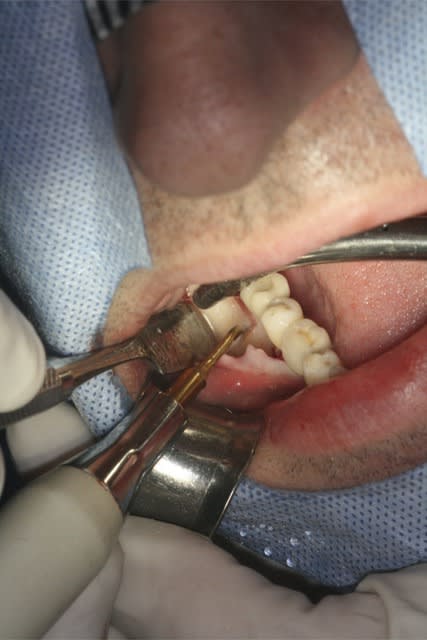

image 2: prélèvement Ramique

image 3 et 4: découpe d'une fine lame allant servir de toit

Désolé pour la qualité, c'est tout ce que j'ai..